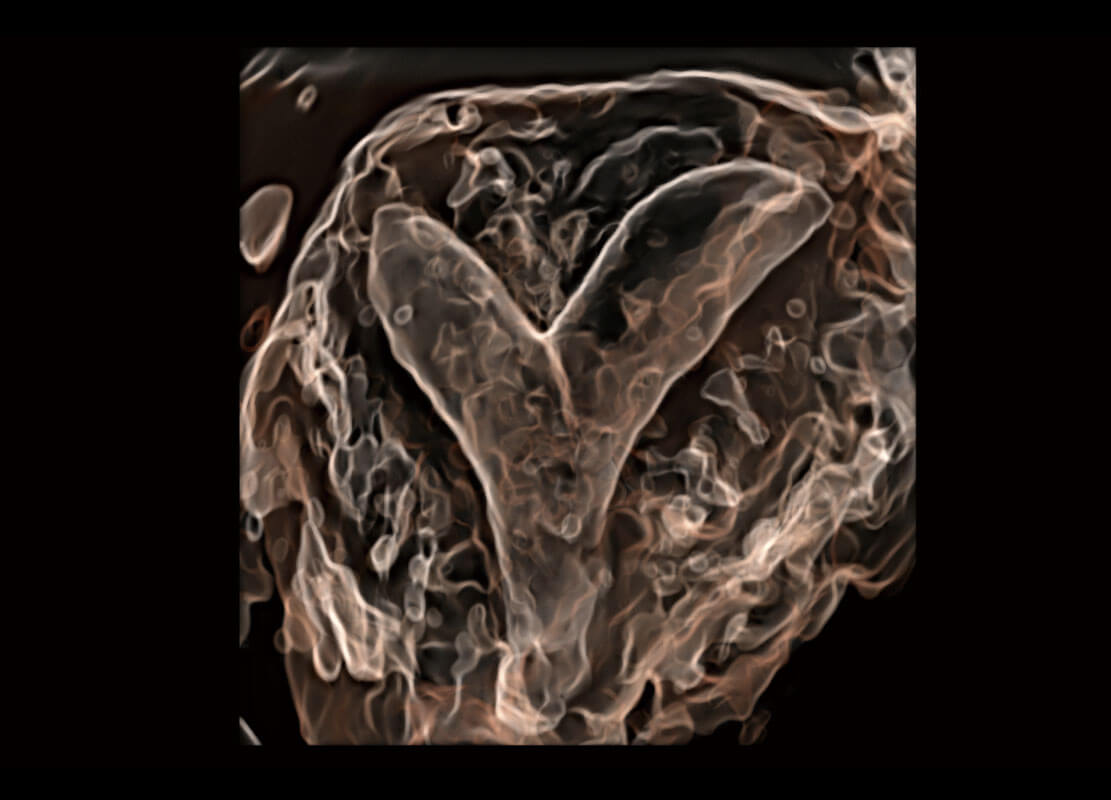

P60搭载一系列胎儿心脏成像技术,实现精细的胎儿心脏评估。

四腔切面

胎心容积成像